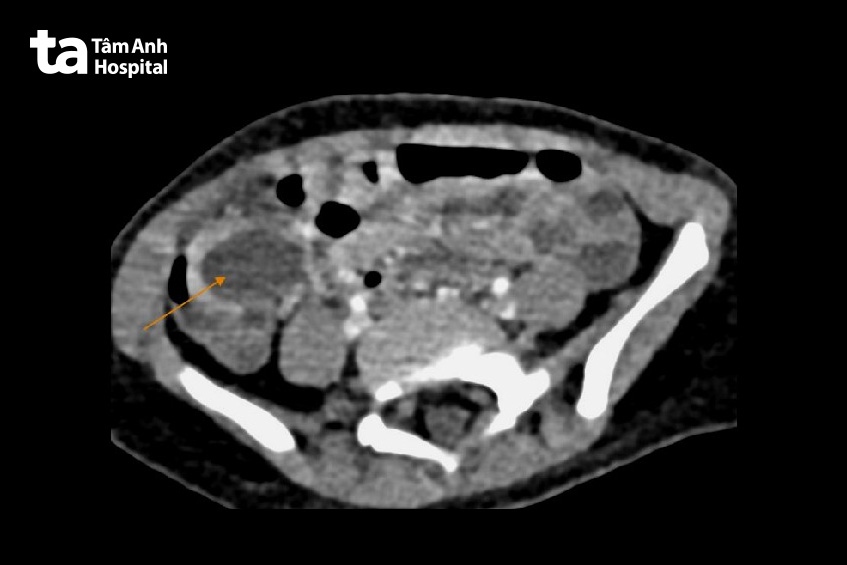

Ngày 29/4, BS.CKI Nguyễn Thanh Sơn Vũ, khoa Nhi, Bệnh viện Đa khoa Tâm Anh TP HCM, cho biết bé gái vào viện cấp cứu trong tình trạng da hơi xanh, sốt, mệt. Bụng bé ở góc hố chậu phải, tại ruột già có một nang kích thước 2x4cm.

“Đây là dị tật ruột đôi bẩm sinh ở đường tiêu hóa, còn gọi là nang ruột đôi, và phẫu thuật là phương pháp điều trị cần thiết để tránh biến chứng”, bác sĩ Vũ nói. Ê kíp mổ nội soi bóc u, khâu lại ruột. Sau mổ ba ngày, bé hồi phục, xuất viện.